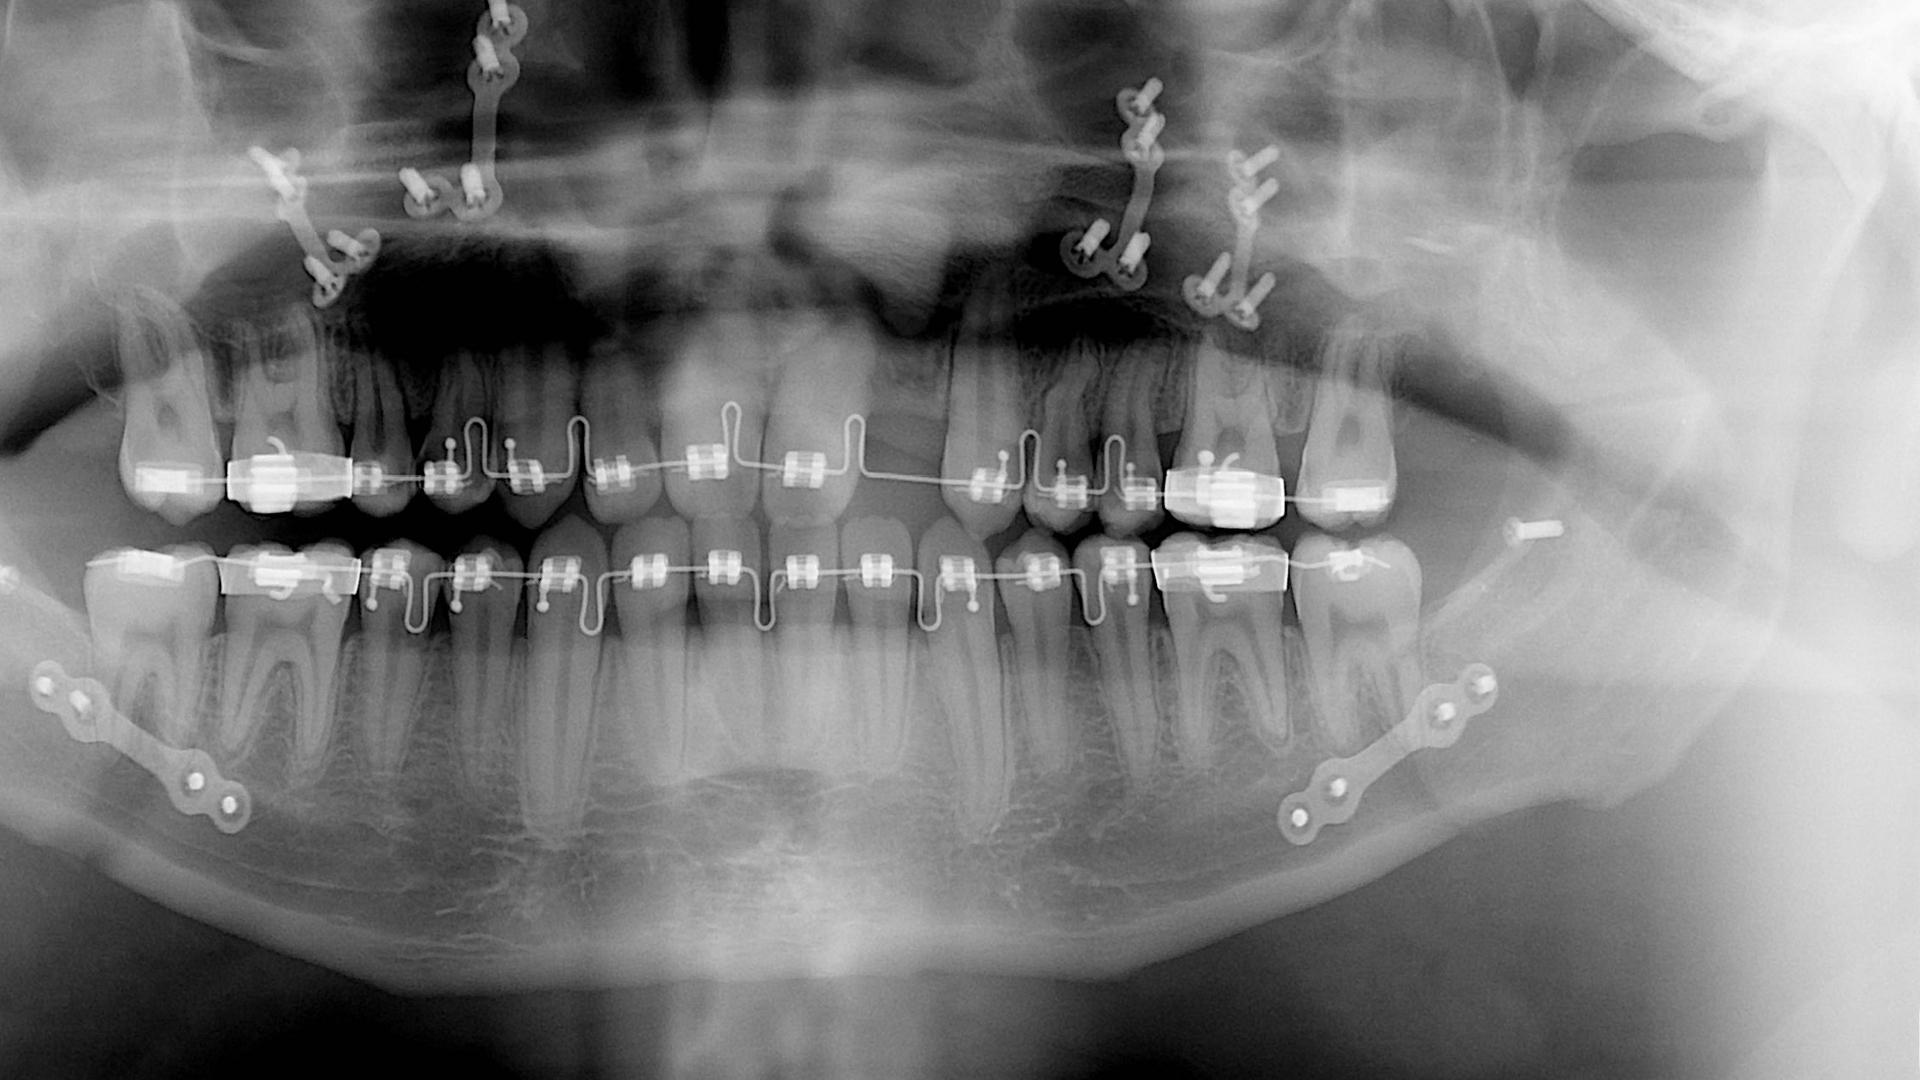

Ortodonti; dişler ve yüzdeki düzensizliklerin (maloklüzyon) teşhisi, önlenmesi ve tedavisiyle ilgilenen diş hekimliği dalıdır.

Ortodontik tedavi her zaman estetik sebeplerle yapılmaz. Estetik kadar fonksiyonda çok önemlidir. Çiğneme, konuşma gibi fonksiyonlarda sağlıklı bir diş kapanışı olması çene yüz bölgesinin sağlığı açısından çok önemlidir. Uygun olmayan diş kapanışları çiğnemede zorluk, çiğneme bozukluklarına bağlı sindirim sistemi problemleri, konuşma güçlüğü, çene eklem problemleri ve buna bağlı eklem ses ve ağrılarına sebep olabilir. Diğer bir unsur ise çapraşık dişlerin temizlenmesi çok zordur.

Çapraşık olan diş dizisi etkin bir şekilde fırçalanamadığı için, arayüz çürükleri, periodontal hastalıklar, yani diş eti ve çevre doku hastalıkları oluşma olasılığı maalesef artabilir. Kötü kapanış diş yüzeylerinde aşınmalara ve buna bağlı olarak dişleri destekleyen kemik ve diş eti yapılarında aşırı strese sebep olabilir. Tedavi edilmediğinde, birçok problem zamanla daha ciddi hale dönüşerek ileri zamanda daha komplike tedavi gereksinimi doğurabilir.